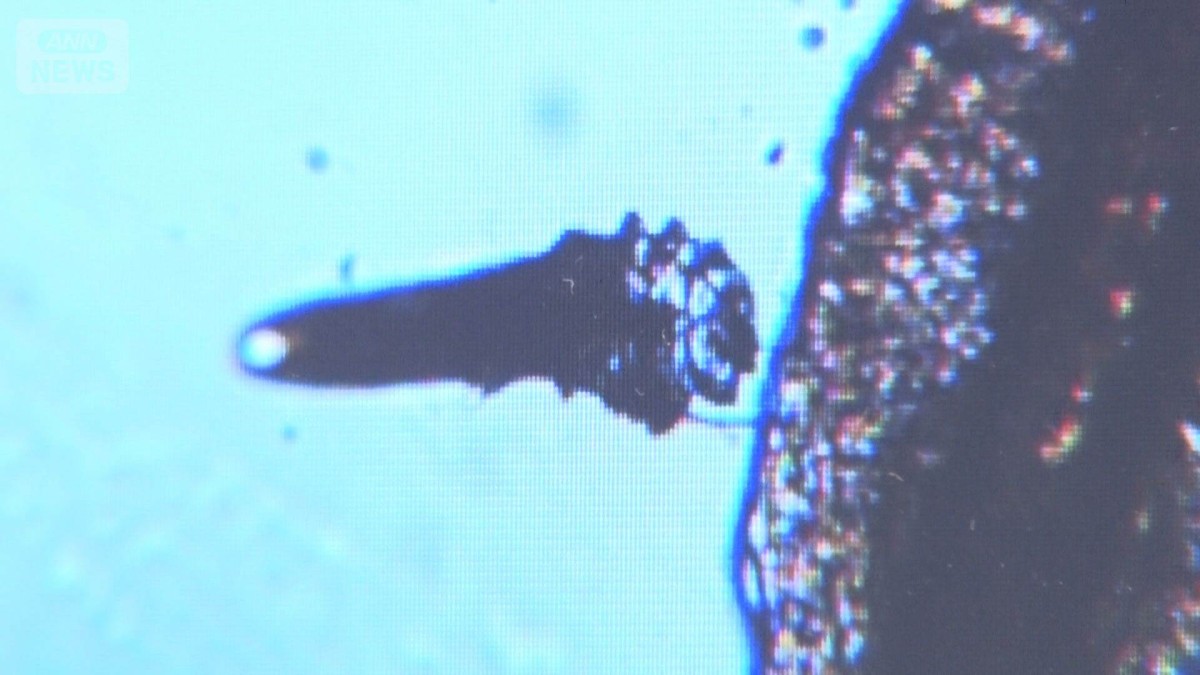

都内の眼科には、目の不調を訴える患者が訪れていました。検査をする人の中には、イモムシのような形をして動く「まつ毛ダニ」が…。

「こんな感じで、やっぱりいるんですよ。虫が」

大きさは0.3ミリほどで、肉眼ではほぼ確認できないまつ毛ダニ。人の顔に生息し、普段は余分な皮脂などを食べてくれます。

「(まつ毛ダニの)発見は非常に難しくて、まつ毛を抜いてみないと分かりません。顕微鏡で見て初めて、いる、いないが分かります」